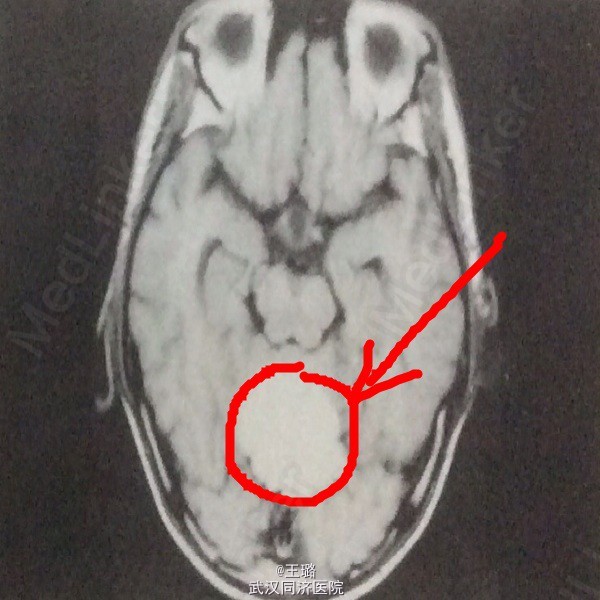

患者,女,37岁 因“呕吐、纳差以及头晕2周”入院,患者近一年来精神萎靡,食欲下降,两周前因感冒后出现呕吐、纳差以及头晕症状,抗感染抗病毒治疗后无好转。

体格检查:体温37.5度,HR:73bpm,血压正常,面部检查眼球水平震颤阳性,颈项强直症阴性。神经反射正常,病理反射未引出。 实验室检查:血常规红细胞降低,血红蛋白白蛋白下降,胆红素正常。 影像学检查:CT示:小脑蚓部有一均匀高密度信号,边缘光滑,略有分叶。MRI示:T1WI显示病灶绝大部分为均匀高信号,与皮下脂肪相近,后部小部分为低、等混杂信号。

诊断:畸胎瘤? 治疗:开颅手术,切除肿瘤,病检示成熟畸胎瘤。术后给予甘露醇降颅压,一周后情况稳定出院。